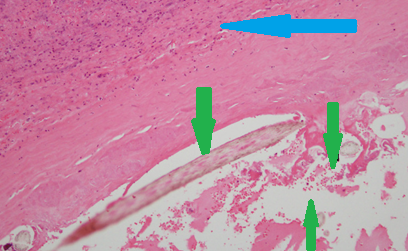

Πράσινα βέλη: Τρίχες. Μπλε βέλος: Ινώδες στρώμα (Ευγενική παραχώρηση Dr. V. Penopoulos)